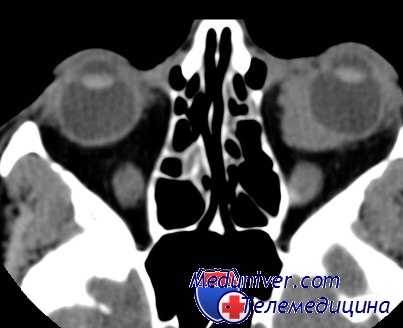

- Томография глазниц. На КТ орбит видны единичные или множественные объемные образования (1 крупная материнская киста и несколько дочерних меньшего размера) с четкими неровными контурами. Средний диаметр эхинококковой кисты не превышает 1 сантиметра.

В отдельных случаях киста разрушает стенку глазницы и распространяется в смежные лобную и верхнечелюстную пазухи, в полость черепа, кавернозный синус. Описаны случаи проникновения эхинококка в глазницу из других полостей. Проанализировав 10 случаев внутриорбитальной кисты, авторы пришли в выводу, что при применении компьютерной томографии черепа предоперационная диагностика более точна [Aouchiche M. et al.].

Молниеносное увеличение паразитарной кисты чревато опасностью постановки неправильною диагноза злокачественной опухоли орбиты со всеми трагическими последствиями. Более информативны УЗИ, КТ и МРТ, которые при эхинококковой кисте позволяют выявлять не только тень паразитарной кисты, но и определять оболочки. Степка кисты перламутрово-блестящая, состоит из двух оболочек: наружной (кутикулярная) и внутренней (герминативная). Оболочки достаточно прочны, что придает кисте определенную эластичность, размер кисты в орбите варьирует: она может быть величиной с грецкий орех или достигать размера крупного куриного яйца.